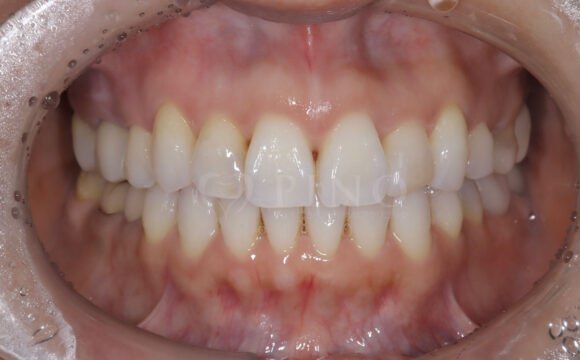

症例3:ワイヤー矯正後の後戻りが気になる(40代女性)

主訴 ワイヤー矯正後の後戻りが気になる 診断名 叢生 治療方法 マウスピース部分矯正 抜歯 なし オルソパルス なし 治療期間 9ヶ月 費用 436,000円 副作用・注意点 矯正後の後戻りを防ぐためリテーナーの使用が必要となる 備考 奥歯に噛み合わせ不良がない場合、部分矯正が適応となる -